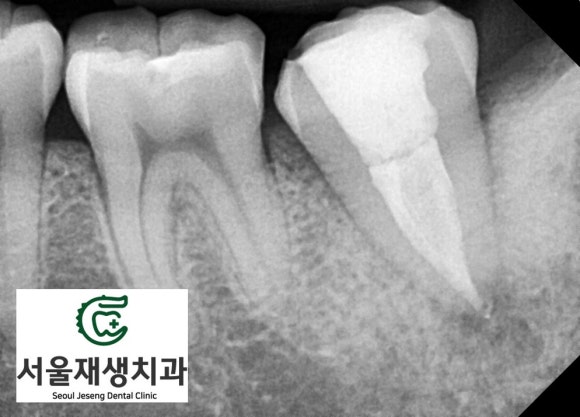

파노라마 엑스레이를

찍어보았습니다.

왼쪽 아래 어금니에

(사진 상 오른쪽입니다.)

신경치료를 받은 흔적과 동시에

뿌리 끝에 매달려 있는

염증 주머니가 관찰됩니다.